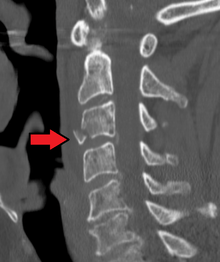

Teardrop fracture of C3 (sagittal CT)